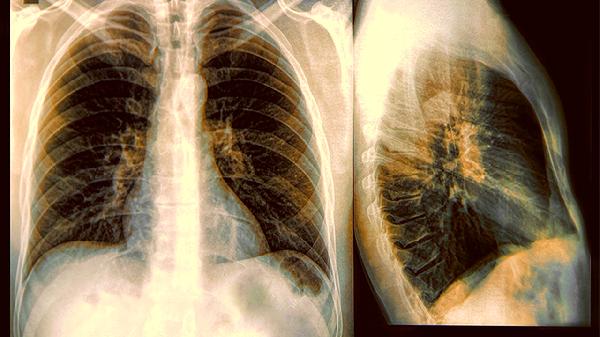

常规体检中的胸片检查不要轻易跳过,对于高风险人群,可以考虑更精准的筛查方式。